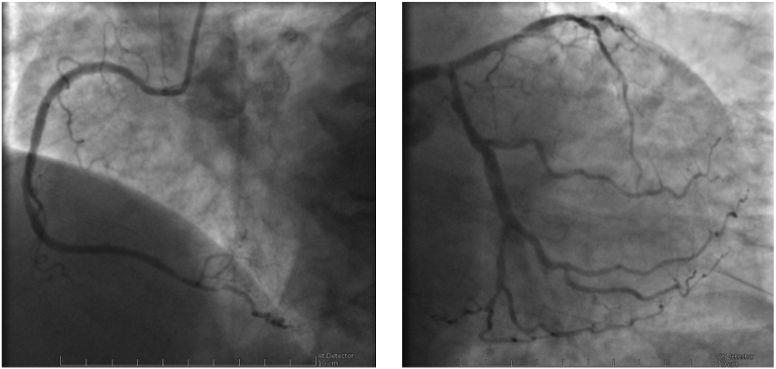

Fig. 2.Coronary angiography images of the case described in Fig. 1 showing diffuse CAD, with severe stenosis of the left main artery. Left: right coronary artery; Right: left main, anterior descendent and circumflex arteries.